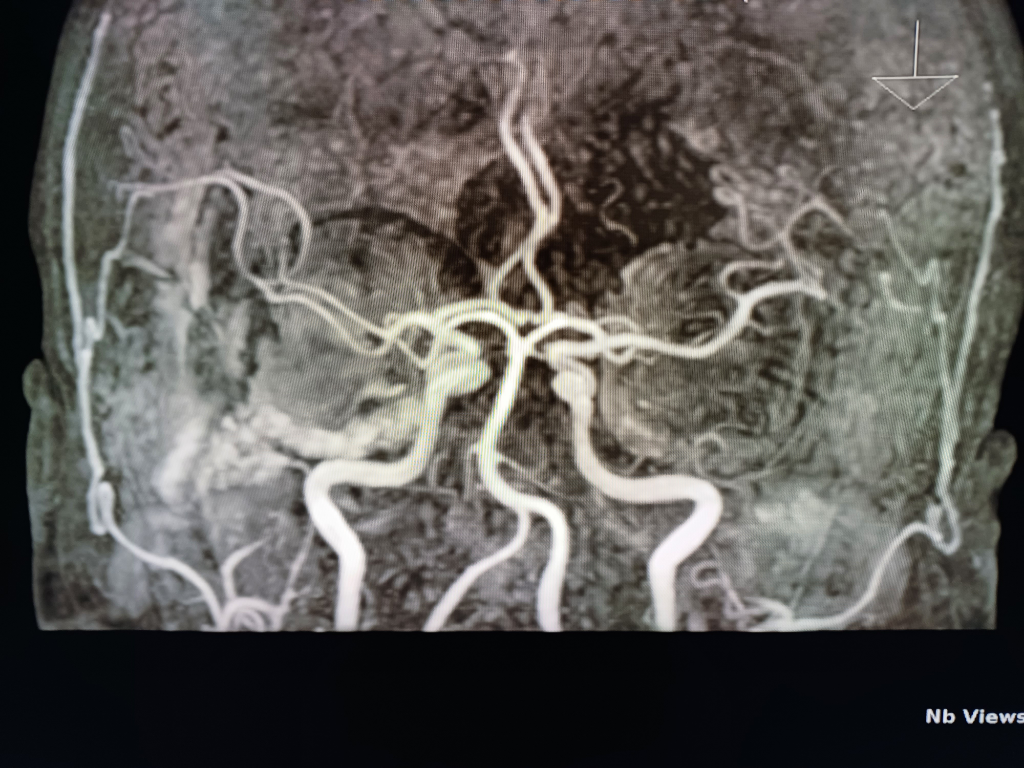

뇌 mri mra를 찍었는데 전문가분들의 고견을 구합니다.

안녕하세요.불편한 어지러움이 한달이상 지속되어 혹뇌쪽 이상이 아닌가 싶어 오늘급하게 mri mra를 촬영하고 왔습니다.결과를 바로 확인할수 있는줄 알았으나 일주일정도 기다려야 판독이 나온다하여 급한 마음에 사진 몇장 첨부하오니 답변해주시면 감사하겠습니다!!

• 2번 째 사진

업로드해주신 MRI 및 MRA 영상은 특별히 이상한 소견이 보이지 않습니다

뇌실질에 이상소견 없으며 뇌혈관이 막여있거나 좁아진 부분도 보이지 않습니다

현재 올려주신 사진만으로는 아주 큰 병변 이 있어 보이지는 않으나, MRI의 경우 연속된 단면을 모두 봐야 병변을 정확히 확인할 수 있으므로 해당 사진들만으로는 병변의 유무를 모두 다 확인 불가능합니다. 추후 판독을 기다려 보시기 바랍니다.